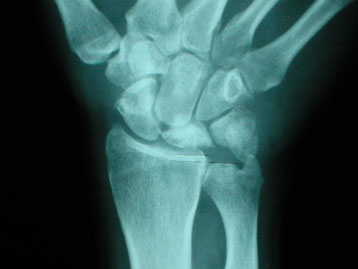

Radiografía simple.

La radiografía puede mostrar cambios en la densidad del semilunar, esclerosis, pérdida de altura, colapso o signos degenerativos en fases más avanzadas. También puede ayudar a identificar variantes anatómicas asociadas, como el cúbito corto.

Estadio III

El semilunar empieza a colapsarse y se distinguen dos subtipos.

Estadio IIIB

Además del colapso, aparece alteración de la alineación carpiana, como rotación fija del escafoides o colapso del carpo.

Estadio IV

Existe una afectación avanzada, con destrucción del semilunar y cambios degenerativos artrósicos en la muñeca.